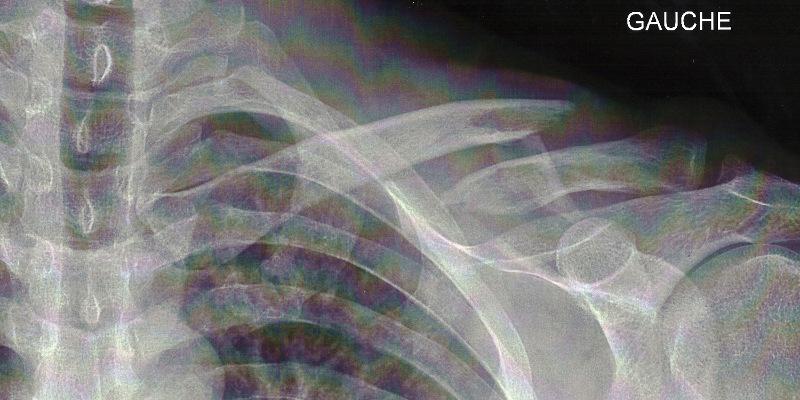

Radio prise juste après la chute. Même sans être expert on se doute qu'il y a un truc louche.

Clavicule gauche